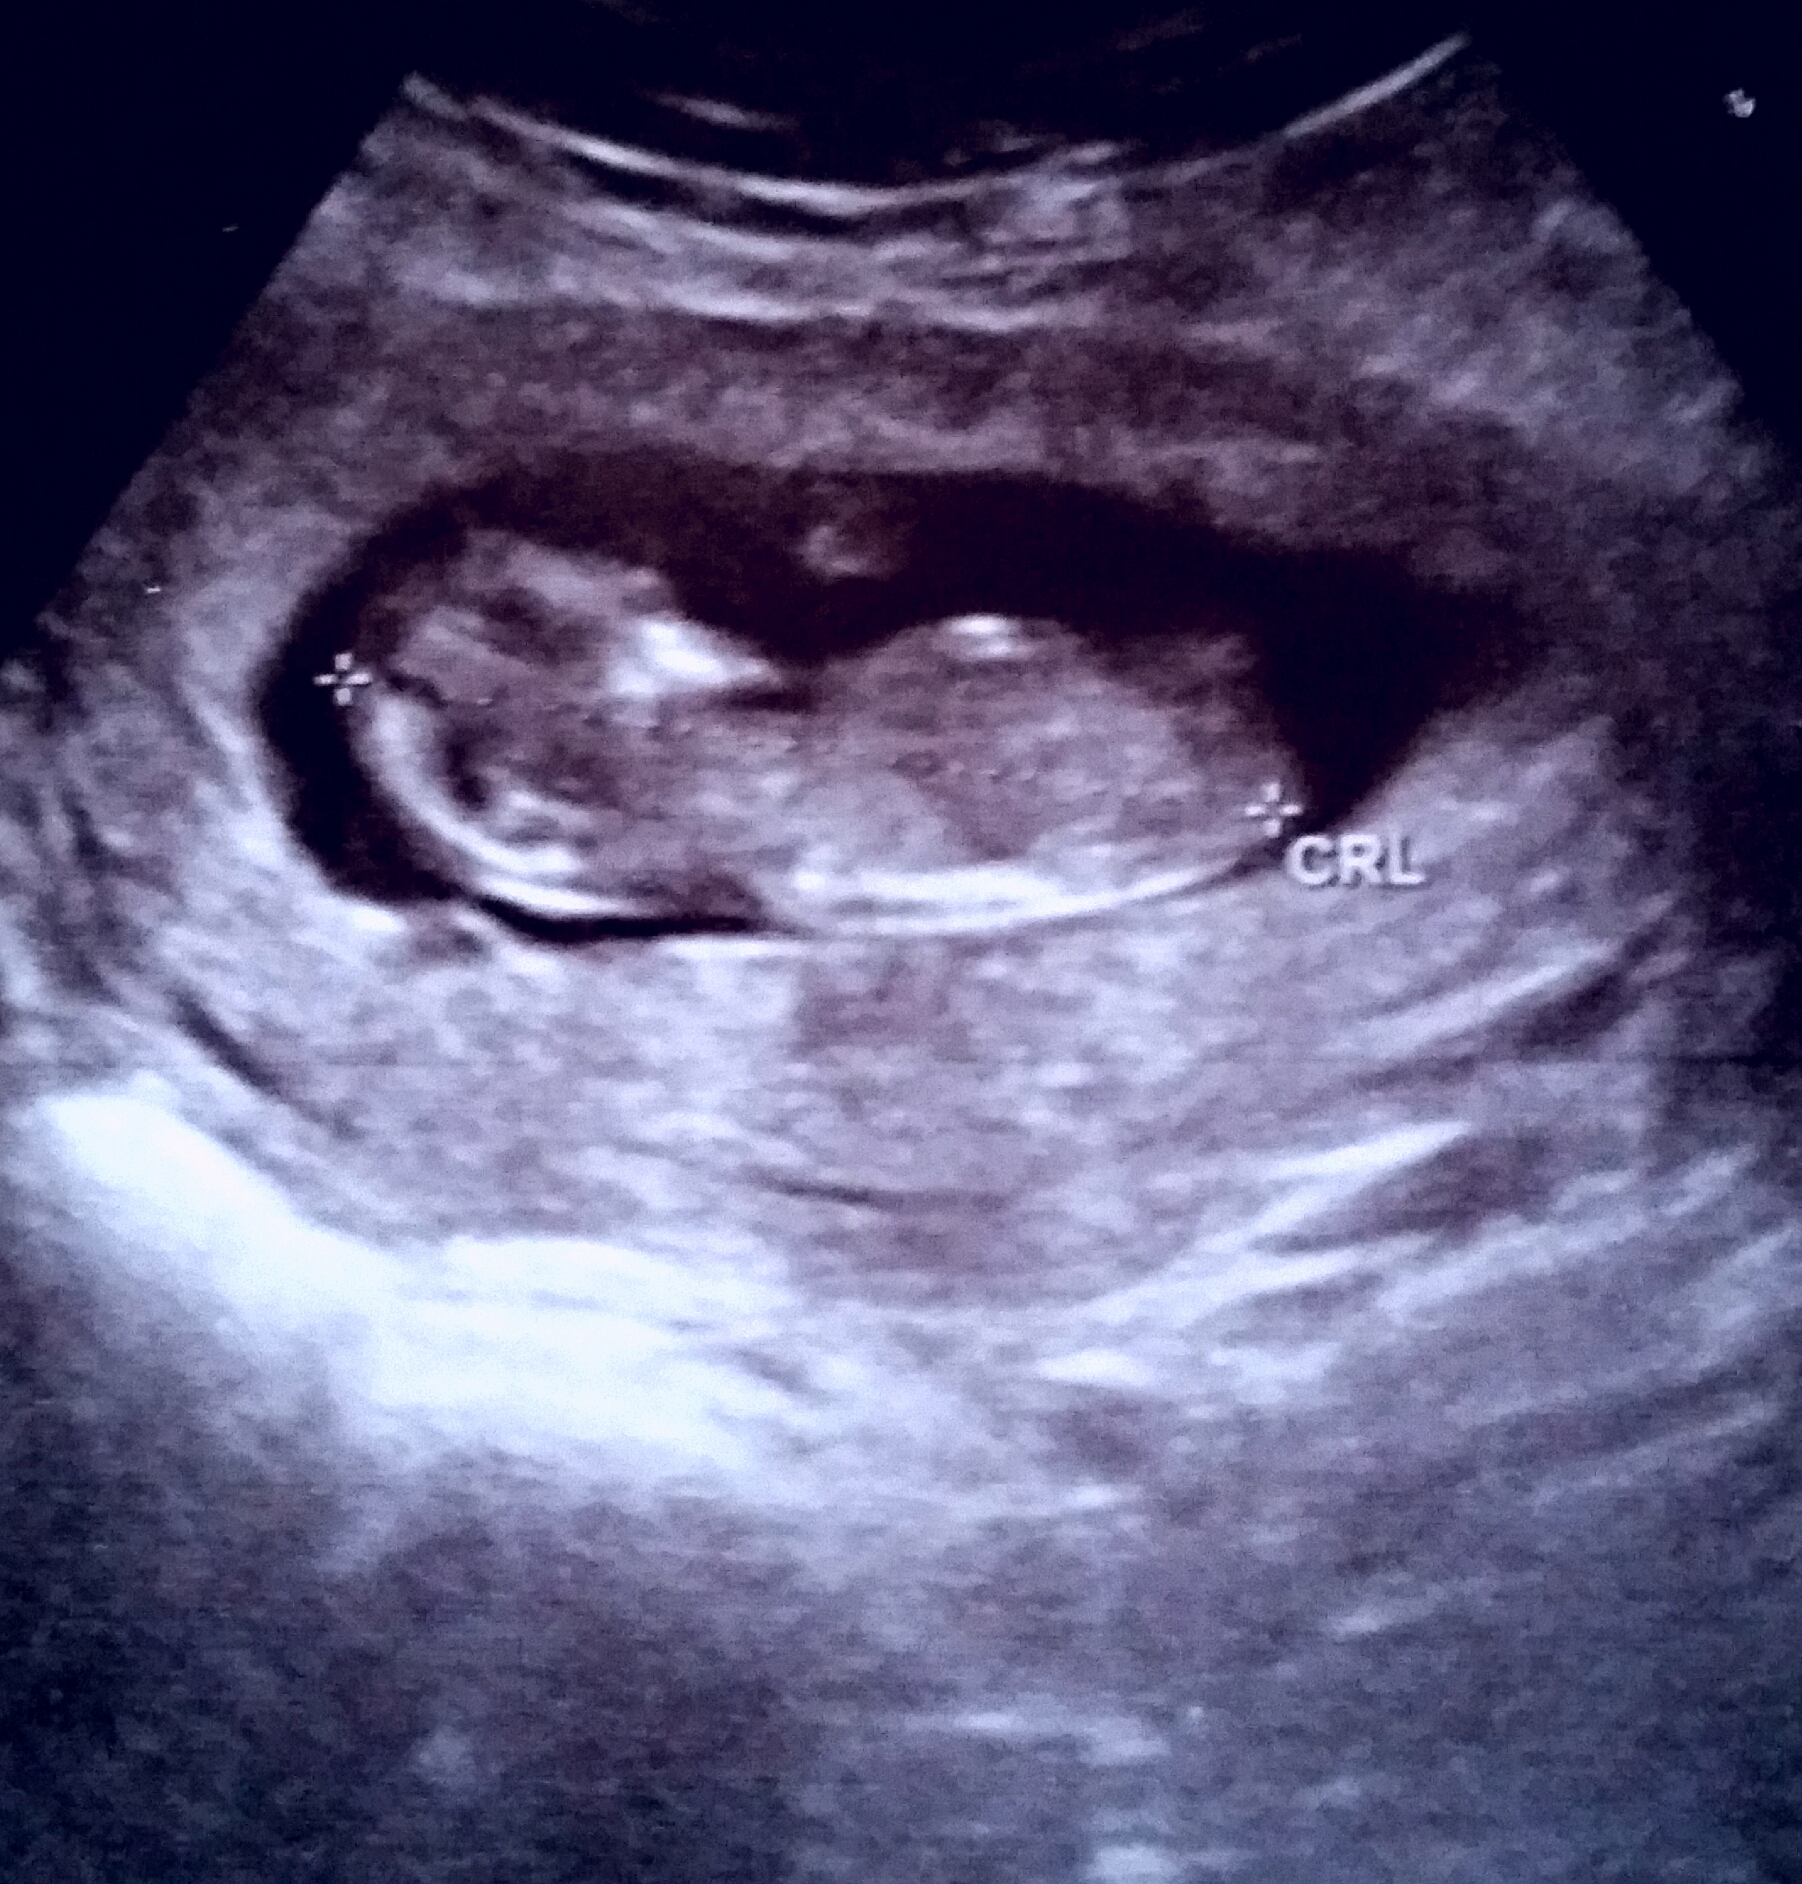

Waht gestation is this bbb??

Ah too early for guesses 11+5

I can't see a nub

no nub

Its good to see your post, babybleau! I think baby is turned away a bit from us, so cant make out nub, but fx this is a little blue one for you! congrats on your pregnancy!

I think blue, not sure that is nub but if it is defo angled hope that's what you wish to hear x

Yep baby was mid rolling over in this pic. Could be the nub but with the blur from the turn there is no telling!